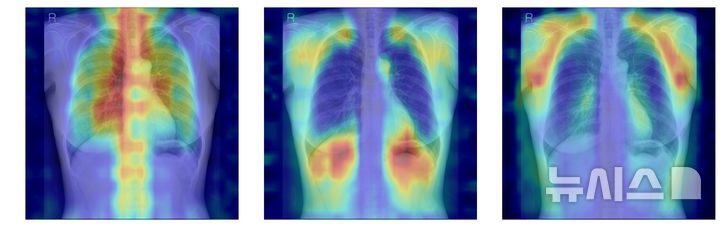

연구팀은 단순 예측 정확도를 넘어 AI가 실제로 어떤 근거를 토대로 판단하는지 검증하기 위해 설명 가능성 평가 체계를 별도로 설계했다. 먼저 차단 분석을 통해 흉부 X선에서 뼈 구조를 전부 가린 상태에서 시작해, 척추만 공개했을 때, 늑골만 공개했을 때 등 특정 뼈 부위를 순차적으로 추가하며 성능이 얼마나 개선되는지를 비교했다. 또 AI의 주목 영역을 열지도 형태로 시각화한 뒤, 실제 뼈가 위치한 영역과 겹치는 비율을 계산하는 IoUbone 지표를 도입해 AI가 얼마나 정확히 골조직에 집중하고 있는지를 정량화했다.

분석 결과, 일반 이미지 기반 파운데이션 모델인 DINOv2에 LoRA 방식을 적용한 조합이 가장 뛰어난 성능을 기록했다. 이 모델은 골다공증 분류에서 AUC 0.93, 95퍼센트 신뢰구간 0.92에서 0.94를 달성했다. AUC 0.9 이상은 통상 우수한 판별력을 의미한다. 동시에 차단 분석과 IoUbone 평가에서 척추와 늑골 등 핵심 뼈 구조에 대한 활용도가 높게 나타나, 예측력과 설명 가능성을 모두 충족한 최적 모델로 평가됐다.

흥미로운 점은 의료 영상만으로 사전 학습된 CheXagent, RAD DINO 계열이 항상 우위에 서지는 않았다는 점이다. 일부 조합에서는 의료 영상 기반 모델이 높은 분류 성능을 보였지만, 중요 영역이 뼈가 아닌 폐실질이나 연부조직에 과도하게 쏠리는 사례도 포착됐다. 반대로 일반 이미지 기반 모델이 LoRA 방식으로 미세조정됐을 때는 상대적으로 적은 재학습만으로도 높은 예측력과 안정적인 뼈 중심 주목 패턴을 보였다.